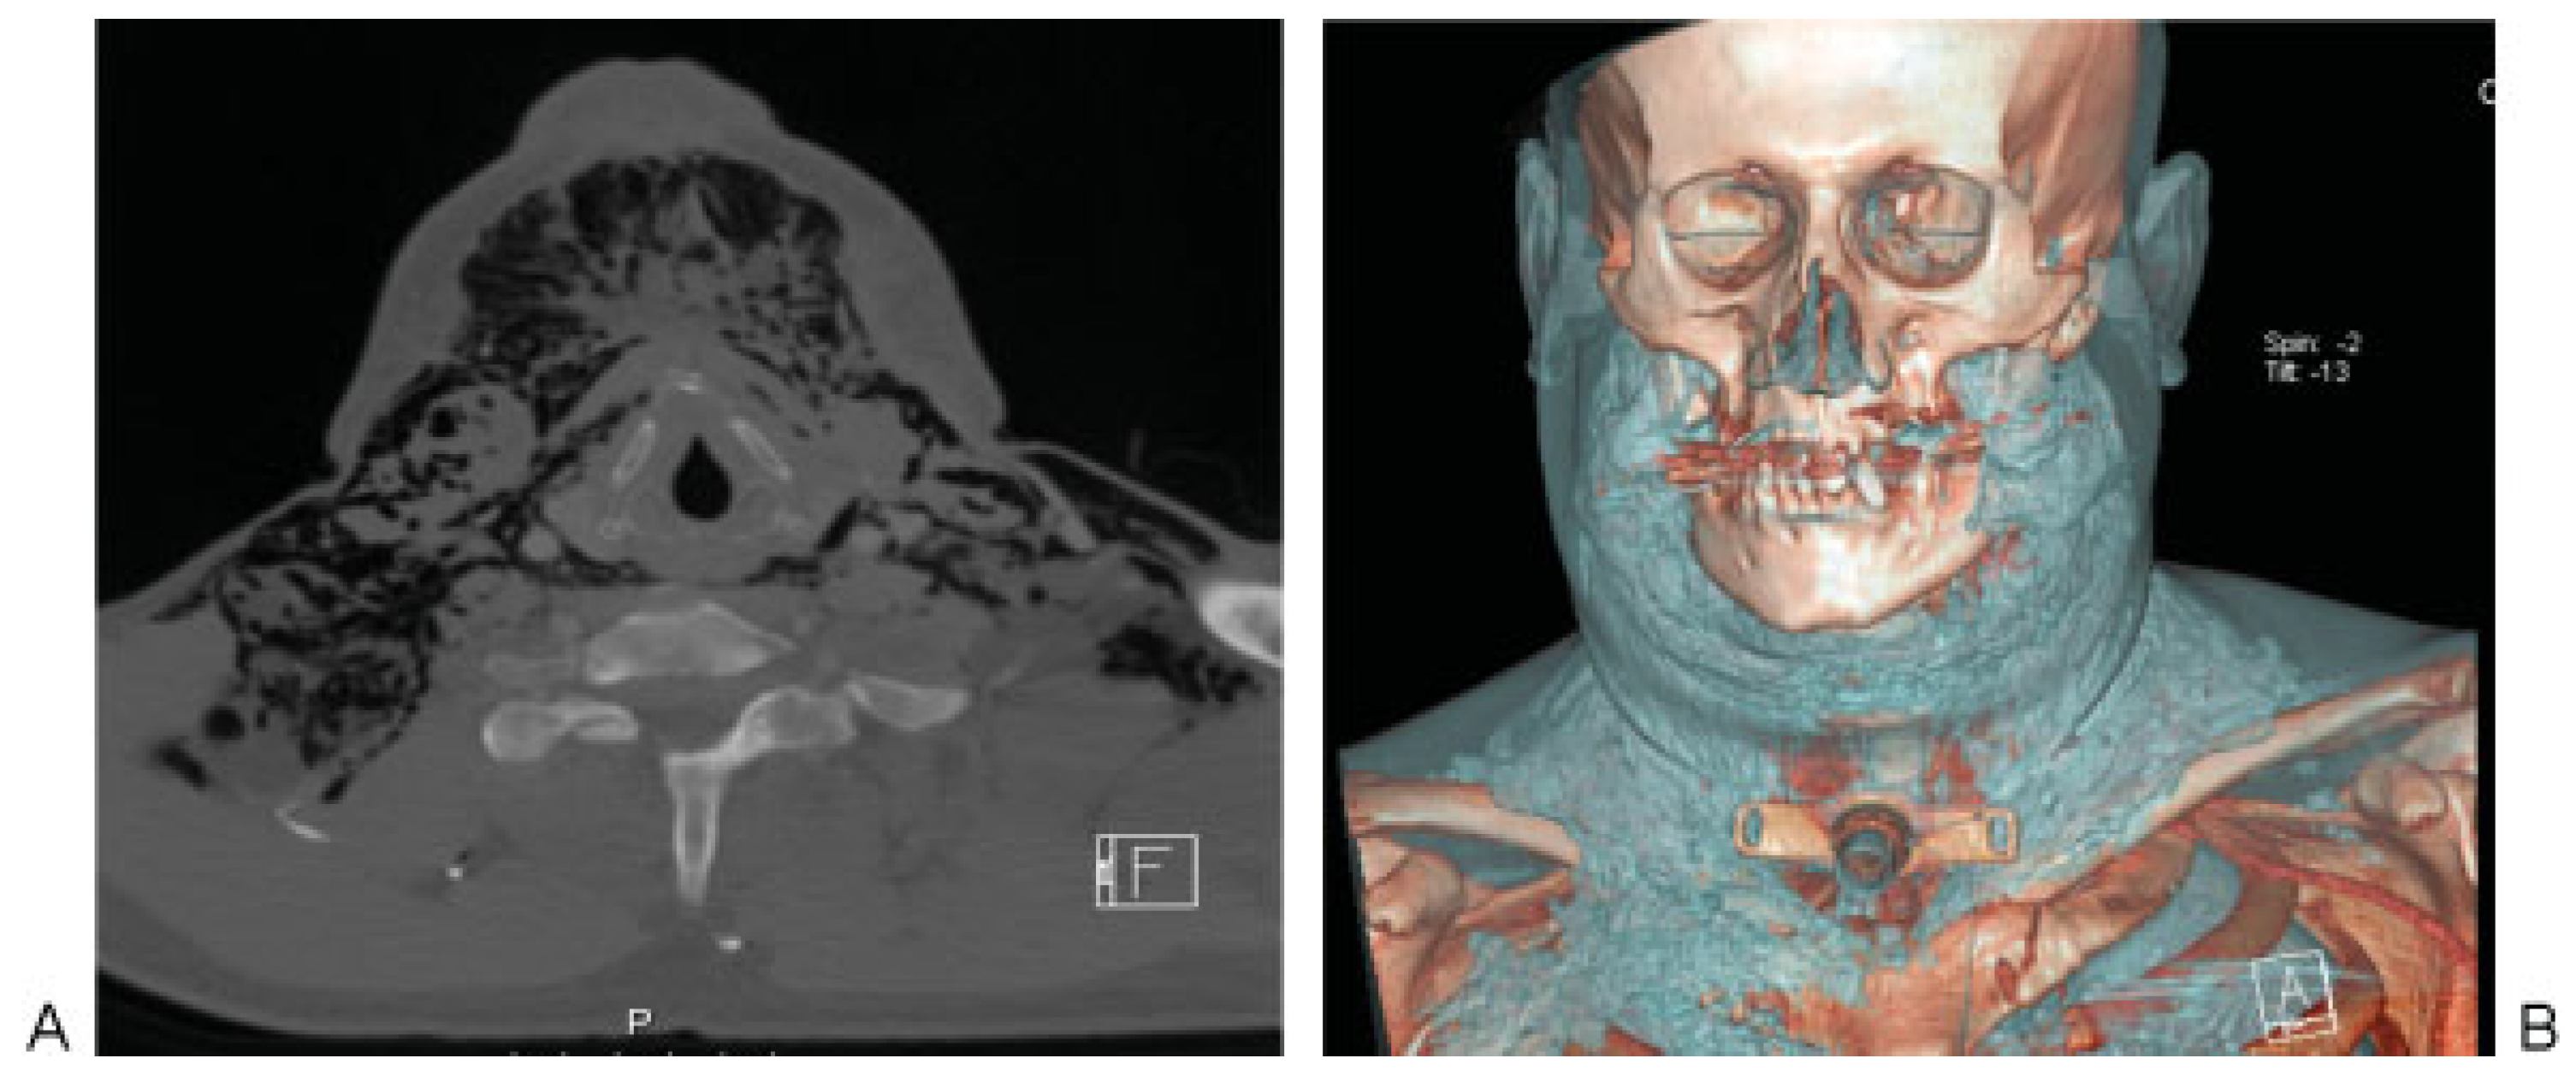

Subcutaneous Emphysema Following Emergent Surgical Conventional Tracheostomy

Case Presentation